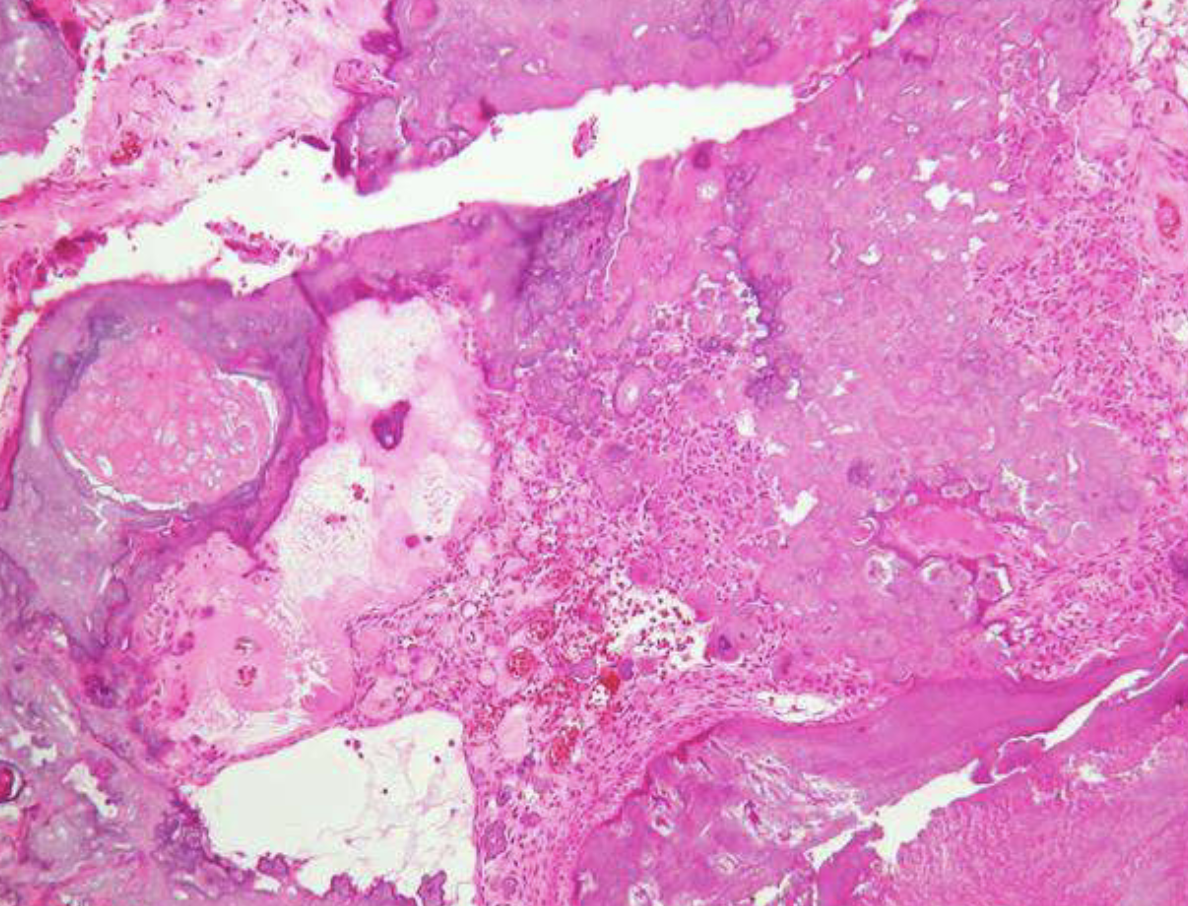

follicular pattern hisopath features of ameloblastomas

nests of epithelium

island centers resembling stellate reticulum

peripheral columnar cells with nuclei polarized opposite basement membrane (sub-nuclear vacuolization)

mature fibrous background